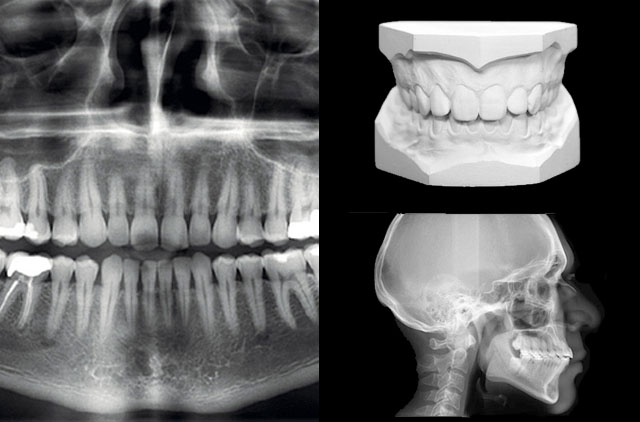

Estudio Convencional

-Panoramica (OP)

-Lateral de Craneo (LC) 8 x 10¨

-Modelos de Estudio en yeso con caja plática rígida

-Lateral de Craneo (LC)